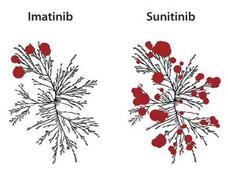

Avapritinib Approved to Treat GIST with a Rare Gene Alteration

Avapritinib (Ayvakit) has been approved for adults with gastrointestinal stromal tumors (GIST) whose tumors have an alteration in a portion of the PDGFRA gene called exon 18. The approval applies to those whose tumors cannot be removed with surgery or have spread.